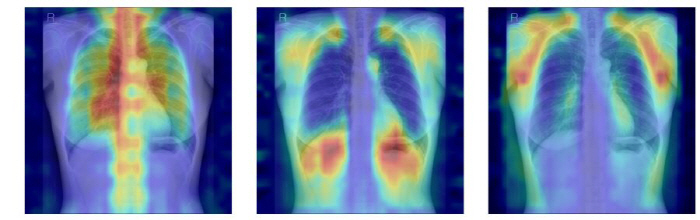

In addition, the research team designed a 'Explainability' evaluation system so that it can check which bones AI actually judges based on. We quantitatively verified whether AI is judged on the basis of clinically important bone structures by calculating how much AI's attention area, which is shown as Grad-CAM, matches the actual bone location by adding a specific bone part while covering all the bones.

As a result, the model applying LoRA method to the DINOv2 model showed the highest predictive performance with AUC 0.93 (95% CI 0.92-0.94). This model was evaluated as an optimal model with balanced predictive power and explainability due to its highest utilization of bone structure and excellent validity in the attention area.